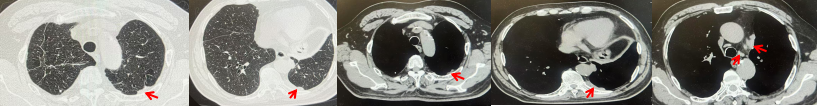

71岁男性,高血压病史20年,口服药物治疗,无糖尿病、心脏病等基础疾病,吸烟史50年,20支/天,已戒1年余,无饮酒史,无肿瘤家族史。2023.11因咳嗽、咳痰行胸CT检查:左肺下叶占位性病变,大小约12mmx8mm(如图5)。2023.11.20行“单孔胸腔镜左肺中下叶切除、肺门及纵隔淋巴结清扫、胸膜粘连松解术”;术后病理:(左肺下叶)结合免疫组化鳞状细胞癌(中、低分化),局部见脉管内癌栓,未见确切神经侵犯,(气管切缘)净。(淋巴结)未见转移癌0/19(4组0/1;5组0/1;6组0/2;7组0/1;9组0/1;10组0/2;11组0/3;12组0/2;13组0/2;14组0/4)。术后分期pT1bN0M0 IA期,术后定期复查。

图5:患者手术前(2023.11)胸部CT肺窗及纵隔窗